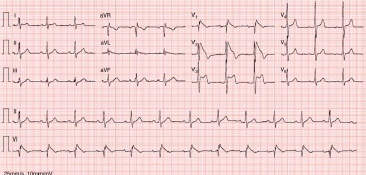

Sobre a patologia ilustrada a seguir, é corretor afirmar que